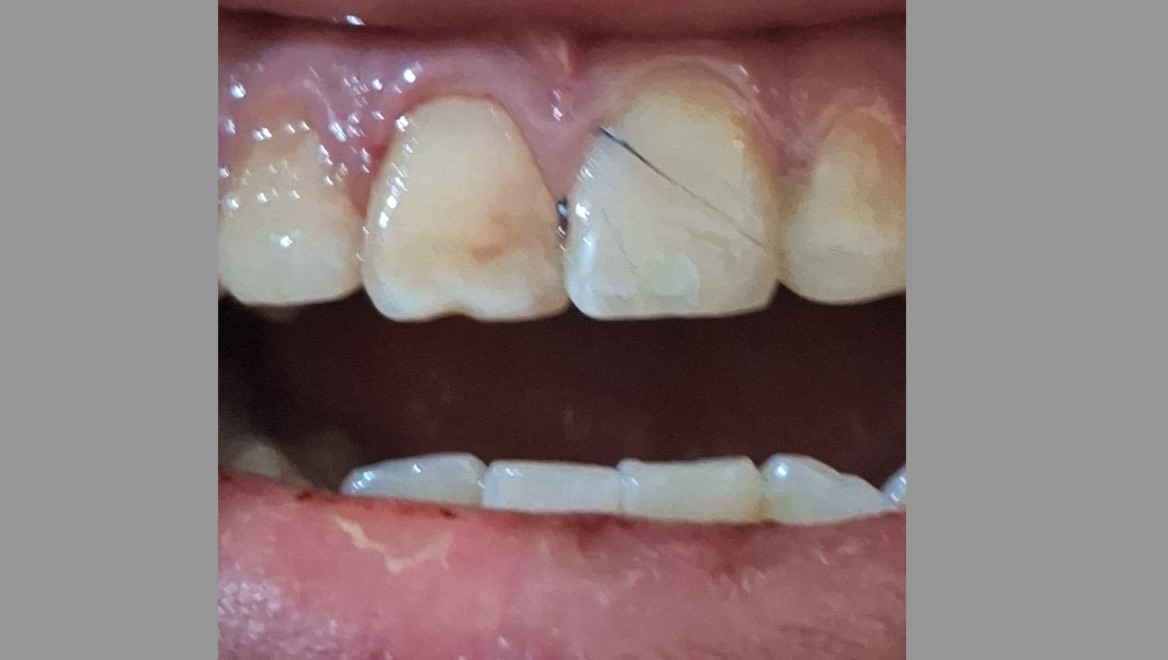

Él se golpeó los dos dientes frontales en un accidente, uno de ellos no se pudo rescatar, siendo necesario realizar endodocia y colocar una corona que usará mientras cumple la mayoría de edad, posteriormente se evaluara si necesita cambio, el otro diente se le fracturó de la raíz en este caso el diente estará en observación durante aproximadamente 6 meses para tratar salvarlo. Buscamos lograr apoyarlo para que pueda solventar los gastos de este tratamiento el cuál no es un proceso fácil, esperamos poder contar con su apoyo